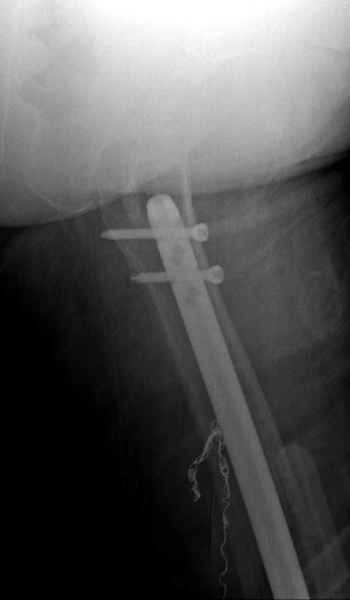

Для предупреждения кровотечения во время рассверливания, за день до операции провели эмболизацию сосудов питающий метастаз. http://radiology.rsnajnls.org/cgi/reprint/150/3/673.pdf (7-11, 12-15-16)

С минимальным рассверливанием и ретроградным методом провели остеосинтез бедра 12 мм гвоздем. (17-20)

Кровопотеря во время операции меньше 100 мл.